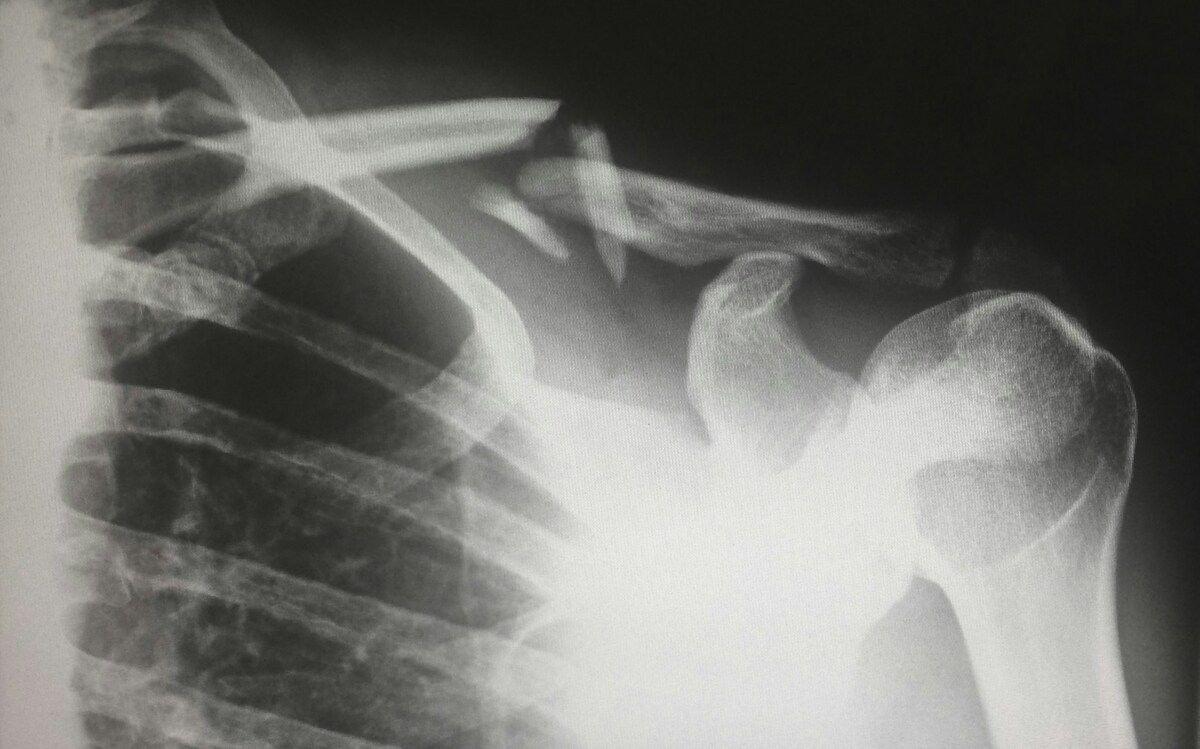

Move-Up se distingue par son portefeuille d’arthroplastie d’épaule, une chirurgie orthopédie considérée comme l’une des plus efficientes et innovantes au monde. Cette intervention chirurgicale vise à rétablir la mobilité d’une articulation en créant un nouvel espace articulaire, souvent à l’aide de prothèses.

L’entreprise propose une gamme complète de prothèses, incluant celles de première intention (anatomiques et inversées), de révision, ainsi que des solutions adaptées à la traumatologie.